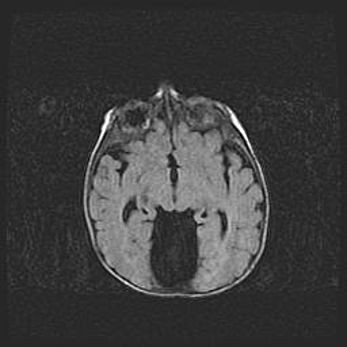

Наружная гидроцефалия с возможной атрофией височных областей.

Возраст: 28 дней

Вес: 3670 г

Пол: мужской

Окружность головы: 38 см

Срок гестации: 40 недель

Гидроцефалия головного мозга у новорожденных – это заболевание, которое характеризуется скоплением избыточного количества спинномозговой жидкости в желудочковой системе головного мозга в результате затруднения её перемещения от места выработки к месту поглощения в кровеносную систему или вследствие нарушения абсорбции. При открытой наружной форме гидроцефалии у новорожденных расширяются и переполняются субарахноидные пространства.

При нормотензивных  формах,  которые,  как  правило,  являются  следствием  перенесенных ишемических  повреждений  паренхимы  мозга,  возможно  сочетание микроцефалии  с нормотензивной гидроцефалией. В основе данных изменений лежит атрофия больших полушарий с преимущественной  локализацией  в  лобно-височных  областях.